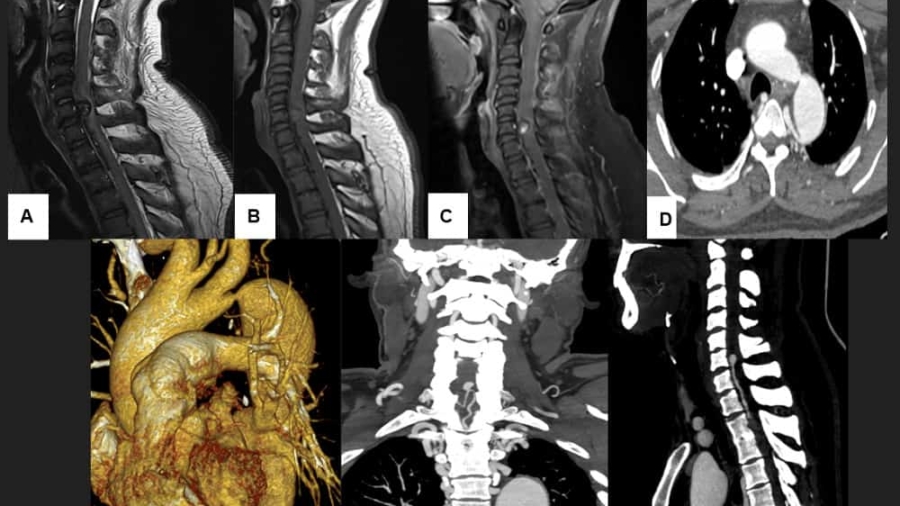

A 36 year old hypertensive male presented with gradually progressive weakness of bilateral upper and lower limb weakness since 1-2 months.